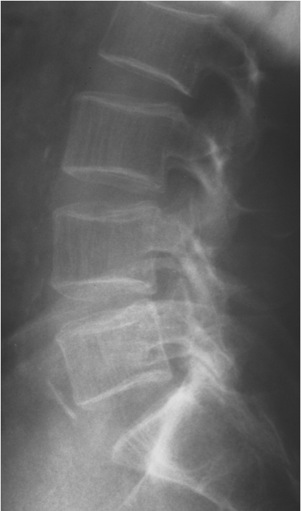

LUMBAR SPINE:

Frontal and lateral views are submitted.  Viewed coronally, there is a mild left convexity with the apex at L3.  The left femoral head and iliac crest are lower than the right by 12mm.  Viewed sagittally, the upper lumbar spine is slightly hypolordotic.

Bone density is moderately diminished, with increased lucency of all osseous structures and vertical striations in the vertebral bodies.  Mild osteophytic proliferation is seen on the vertebral bodies from L2 through L5.  Calcific plaquing is visible along the course of the abdominal aorta.

IMPRESSIONS:

1.	Atherosclerosis.

2.	Moderate osteoporosis.  Follow up is recommended.

3.	Mild spondylosis, L2 through L5.

4.	Apparent 12mm short left leg.  Clinical correlation is recommended.

5.	Postural alterations as described above.